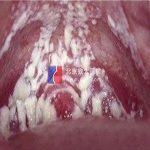

隐性尿道下裂,就是尿道口离阴道口过近,做爱时易把阴道分泌物挤压入尿道内,引起尿道不适和炎性反应,表现为做爱后出现泌尿系感染症状,比如尿道发热,尿急,尿痛,用点抗生素尿道炎就能缓解,但随后就会出现阴道炎,性活动活跃期尤为明显。其实很多女性都有类似的问题,但是很多医生并不认识此病,导致乱用抗生素,阴道菌群失调,阴道炎与尿道炎交替出现。

尿道-阴道隔离术,就是分离阴道和尿道隔膜,在它们之间镶嵌一个生物隔离带,将尿道口位置前移2cm,这样做爱时就不会把阴道分泌物挤压入尿道,阻断了阴道-尿道交叉感染的渠道。手术在静脉和局麻联合下进行,术中术后没有痛苦,留观1-2天,不用刻意休息,2周后可以恢复性生活。但是此术对医生要求很高,还需要生物隔离带,所以手术费相对也高。